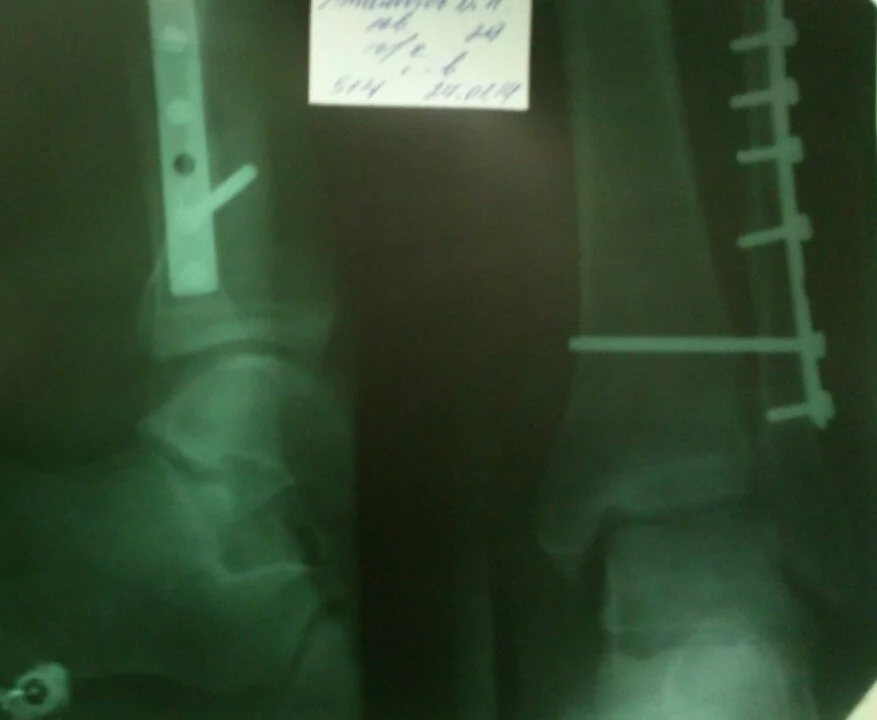

Диагноз:закрытый перелом наружной лодыжки левой голени с разрывом межберцового синдесмоза. 24.01. сделали операцию , поставили пластину . После 4х недель 21.02. сняли гипс и назначили лфк . 21.03. врач хочет меня выписать, и но я не могу еще обходится без костылей , и нормально передвигаться особенно в общественном транспорте. Работа у меня все время на ногах.